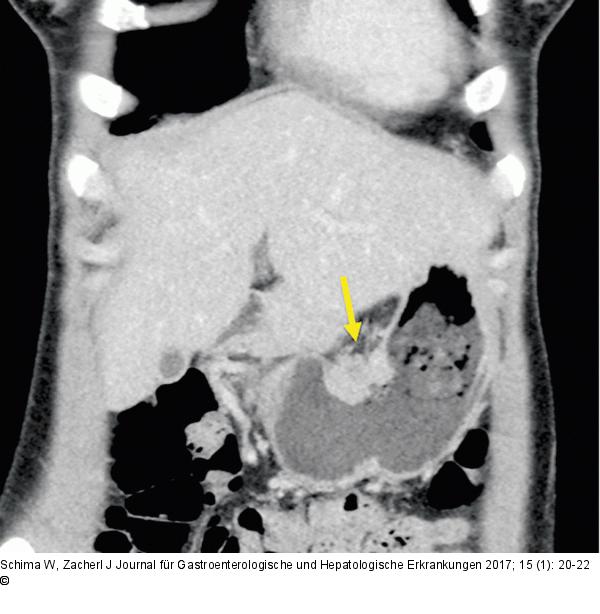

Abbildung 1a: Antrum-Karzinom

Die coronale MDCT zeigt das wandüberschreitende Antrum-Karzinom (Stadium T3). |